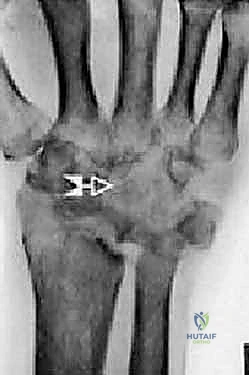

1. التخطيط الجراحي المسبق

قبل العملية، يتم إجراء صور أشعة سينية (X-rays) وأشعة مقطعية (CT scan) ثلاثية الأبعاد. تساعد هذه الصور الدكتور هطيف في تحديد حجم التلف بدقة، واختيار الحجم والنوع المناسب للمفصل الصناعي (والذي يتكون عادة من أجزاء معدنية من التيتانيوم ومكونات بلاستيكية عالية الكثافة من البولي إيثيلين).